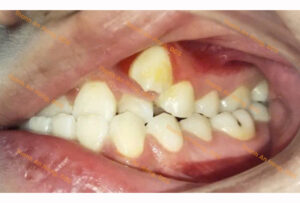

HÌNH ẢNH THỰC TẾ

Sắp đều răng trong độ tuổi tăng trưởng với mắc cài